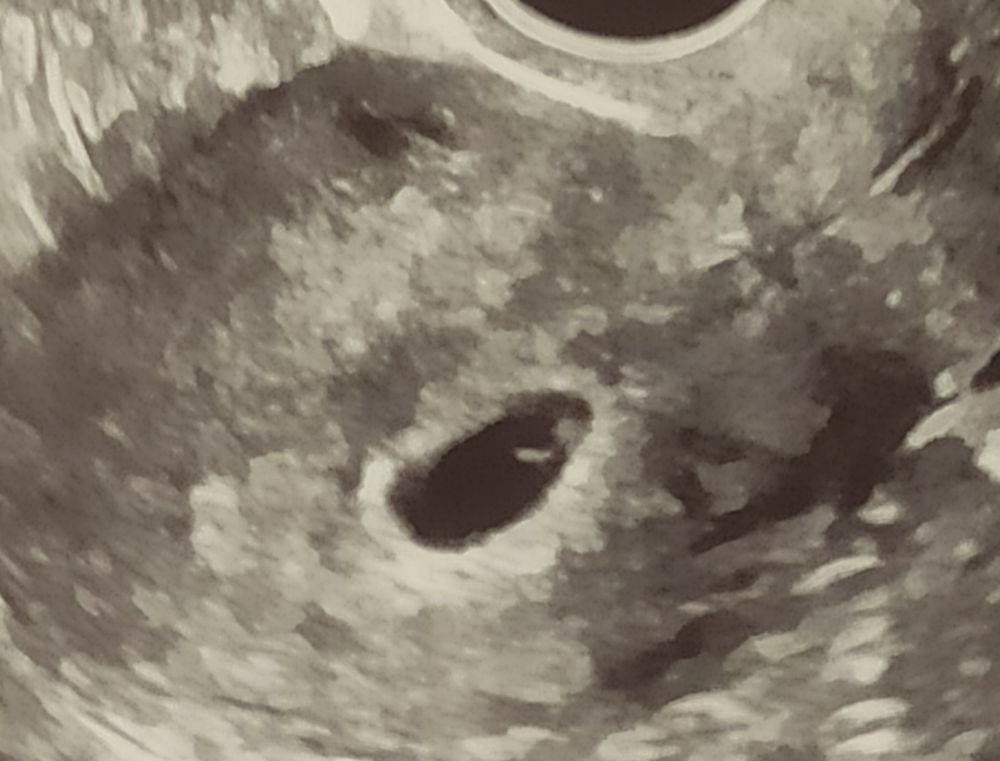

УЗИ на 27 дпо (5+6)❤🤞🤞🤞

ПЯ 12 мм, ЖМ 3 мм, КТР 2,4 мм, ЧСС 108 уд/мин. Я видела на экране как стучит сердечко❤, чувства неописуемые😃😇, как в первый раз, я верю, что всё будет хорошо 🙏🙏🙏 и мы будем расти и развиваться🤞🤞🤞